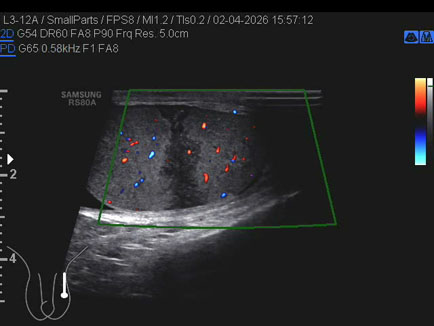

Data inserimento: 03/04/2026

Ecografia del: 12/03/2026

Strumento: Esaote MyLab Eight

Sonda: Convex Multifrequenza 1-8 MHz

Età Paziente: F 66 anni

Motivazione dell'esame: follow up per angiomiolipoma renale destro

Commento all'esame: le immagini ed il video documentano al rene destro, in sede corticale polo inferiore, immagine iperecogena, a margini definiti, delle dimensioni di 25 x 23 mm, senza segni di vascolarizzazione, da ricondurre, come prima ipotesi, ad angiomiolipoma.

Conclusioni: angiomiolipoma del rene destro (angiomyolipoma of the right kidney).

In collaborazione: Dr.ssa Marica Manfredi - Ancona, Dr. Ilir Qose - Ancona

Presentazione: Dr. Massimo Dolciotti - Ancona

Elaborazione digitale: Andrea Dini - Ancona